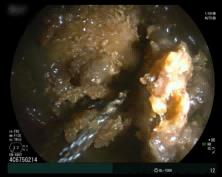

在麻醉团队的配合下,进展顺利。小肠镜入肛后,在距回盲瓣约70厘米处,发现了“罪魁祸首”——一枚直径约为10厘米的巨大粪石,相当于成年人拳头大小。郭勤果断操作,上演“碎石术”,使用圈套器将粪石逐步分解粉碎后,再用网篮带出碎石,如此往复。她始终小心翼翼,手法轻柔,以免误伤肠壁。

团队常规的小肠内镜下治疗1个多小时就可以完成,这次,郭勤团队和粪石鏖战了4个多小时。堵塞的管道一点点被清理通透,吸出2000多毫升粪水,最终解除梗阻。